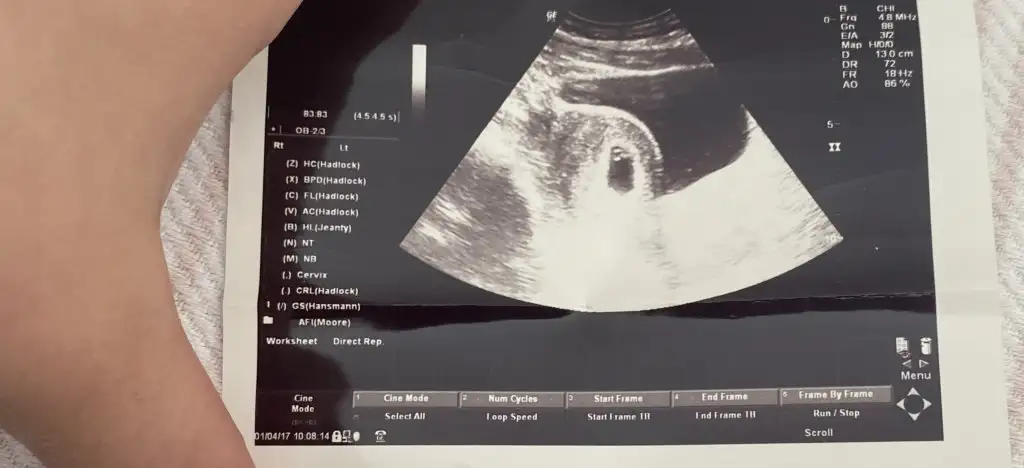

5 ve 14. haftaya kadar olan ultrason fotolarınızı paylaşın. Vajinadan mı yoksa karından mı çekildiğini ve kaç haftalık olduğunu da mutlaka belirtin.

mesaj atabilirsin bana, neden buraya yüklenmedi ki?Fotoğraf paylaşımiyorum yardımcı olur musunuz

9+5 karından usgmesaj atabilirsin bana, neden buraya yüklenmedi ki?